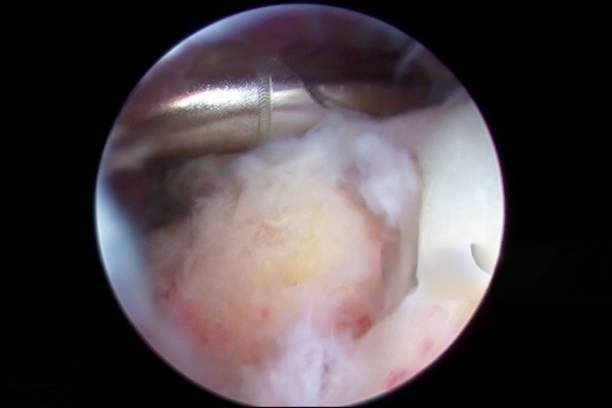

During the procedure, Dr. Gautam uses an arthroscope—a small camera inserted through tiny incisions. With the help of specialized instruments, he examines the shoulder joint in detail. Because the surgery is performed arthroscopically, patients experience less trauma, minimal scarring, and a quicker recovery compared to open surgery.

ASD focuses on creating more room within the subacromial space. To achieve this, Dr. Gautam carefully removes bone spurs or excess bone growth beneath the acromion, the bony structure at the top of the shoulder. As a result, pressure on the rotator cuff tendons decreases, leading to significant pain relief and smoother movement.